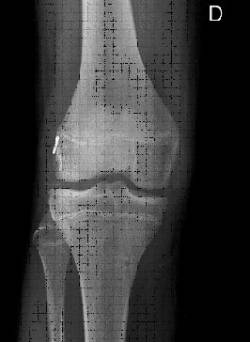

Las lesiones ligamentosas también se encuentran presentes en pacientes pediátricos no debiendo ser infravaloradas por la edad del paciente. Los traumatismos rotacionales con derrame articular y la presencia de sangre en el mismo son indicativos de la posible lesión del ligamento cruzado anterior.

Un mal funcionamiento de este ligamento puede determinar un deterioro articular en una rodilla en crecimiento siendo muy difícil imitar la actividad deportiva de este grupo de pacientes .